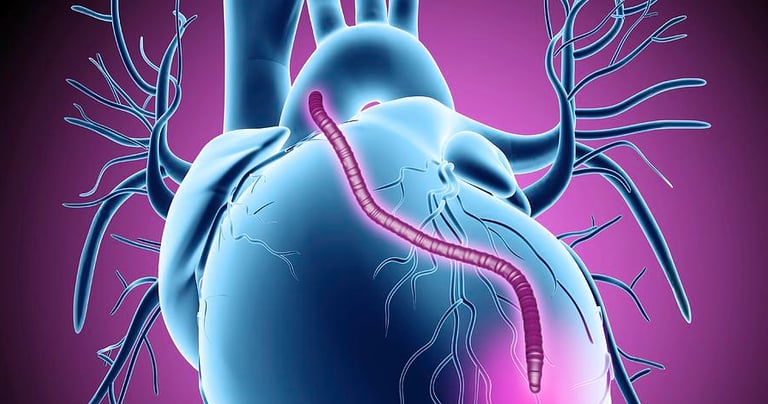

Radial Artery Mapping for CABG

The radial artery is a valuable conduit for a coronary artery bypass graft with excellent long-term patency rates. The ultrasound assessment identifies collateral circulation, which is important to ensure adequate blood flow to the hand after the radial artery is harvested.